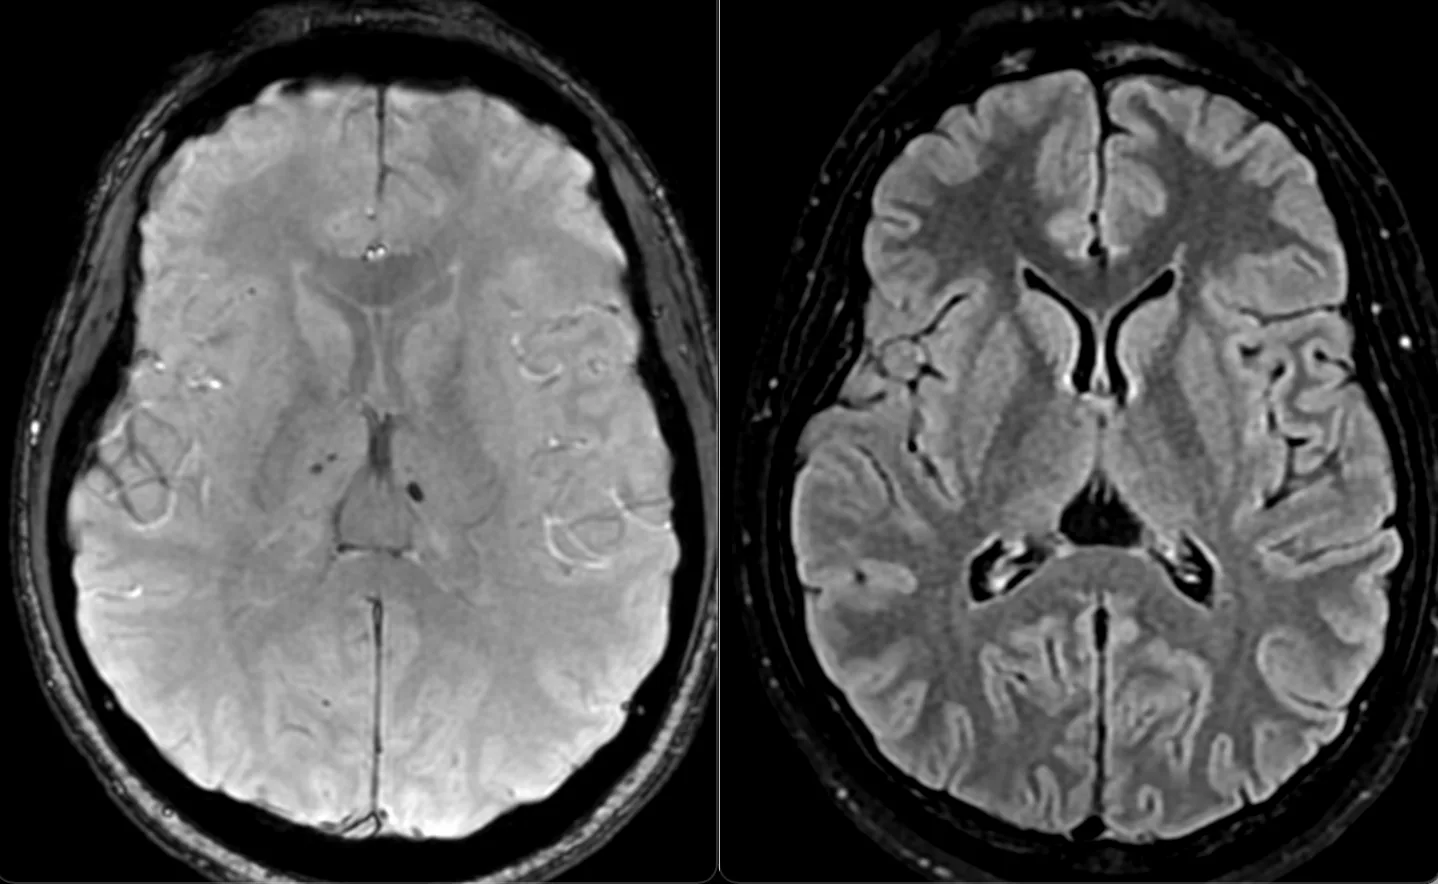

Мужчина 35 лет, месяц назад упал с высоты двух метров, сейчас не полностью ориентирован в месте и времени. Типичная (кроме мозжечка справа) картина травматического аксонального повреждения 3 степени (с поражением ствола). Множественные мелкие точечные и линейные микрокровоизлияния, вокруг части из них видны глиоз/отек. А вот в мозжечке, реально, нечасто такое увидишь. Но бывает. Типа, как вот здесь: